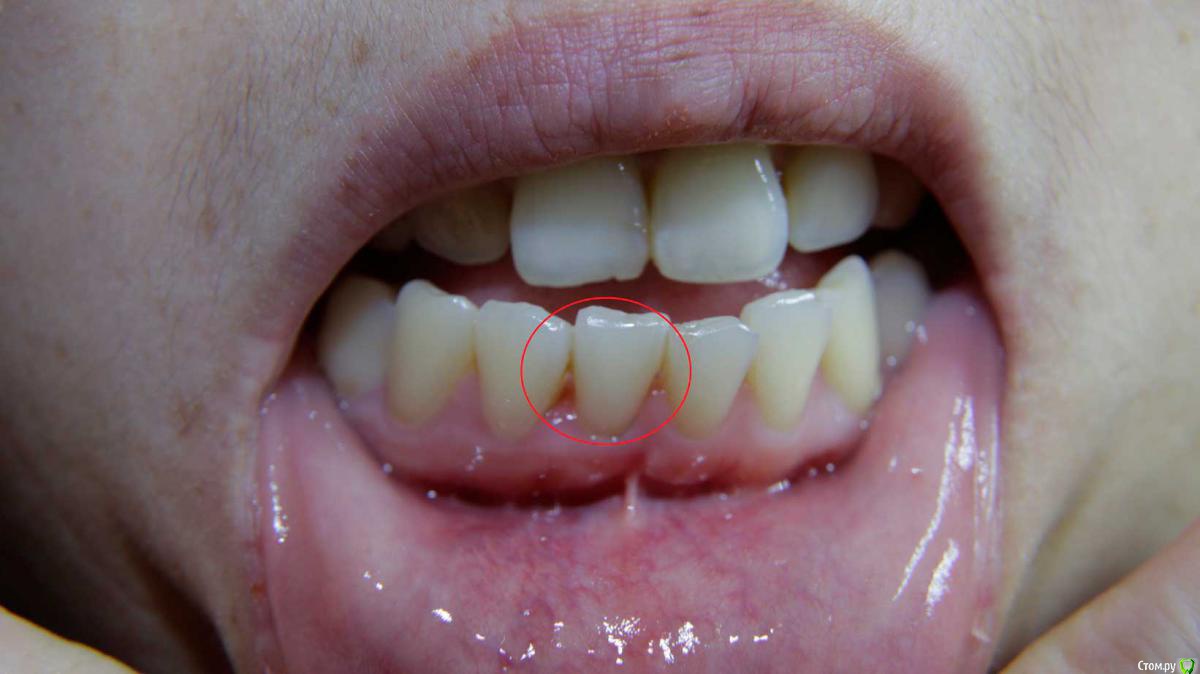

Яна Баировна Опубликовано 15 декабря, 2016 Поделиться Опубликовано 15 декабря, 2016 (изменено) Уважаемые врачи прошу подсказать по моей проблеме. У меня полтора месяца назад начали кровоточить десны между зубами 4-5-6 с правой, нижней стороны. Сходила в гос поликлинику к стоматологу - терапевту, которая сказала что у меня гингивит и сделала чистку ультразвуковую, после которой у меня ещё начали кровоточить передние нижние зубы. Врач посоветовала полоскания содой, солью и йодом чтобы уменьшить отёк, но если не улучшится то обратиться к парадонтологу. Спустя 10 дней отёк уменьшился но кровоточивость оставалась. Затем я сходила к другому врачу - пародонтологу, который сказал, что нужна глубокая чистка, (по цене не дёшево). Я уведомила его о том что неделю назад уже делала чистку, но парадонтолог сказал что нужна именно глубокая чистка, а также он направил сделать панорамное ОПТГ. Так же при визуальном осмотре он сказал что наблюдается начальная стадия парадонтита на однёрке снизу справа. Далее я пошла к первому врачу из поликлиники, которая чистила мне до этого, на дочистку. Но забыла выяснить, сделала ли она глубокую чистку на этот раз или это снова что-то не то?. Параллельно я консультировалась с третьим врачом, которая при внешнем осмотре сказала, что на переднем нижнем зубе образован "патологический" карман и его нужно срочно лечить - признаки пародонтита. Я сходила и сделала снимок панорамный, который тут представлен, но консультации по нему ещё не получила. По снимку не совсем понятно, это брак снимка (засвеченный и размытый именно тот зуб про который говорили врачи)? Подскажите, на снимке в каких местах виден пародонтит и вообще есть ли он? Уважаемые врачи, мне на визитах все говорили разное и тянули на лечение именно у них, но хотелось бы независимого мнения от специалиста! Не хочу и не могу каждый разплатить за возможно ненужные процедуры. Пожалуйста подскажите что-то по снимку. Изменено 15 декабря, 2016 пользователем Яна Баировна Ссылка на комментарий

red_butler Опубликовано 16 декабря, 2016 Поделиться Опубликовано 16 декабря, 2016 Для полноценных ответов нужен очный осмотр, но по снимку похоже что пародонтит уже есть. Требуется консультация ортодонта и ортопеда. Ссылка на комментарий